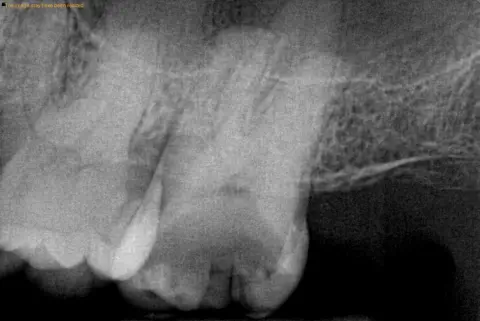

That’s why routine exams and X-rays are essential—they detect problems before you feel them.

- Routine X-rays (to catch hidden decay)